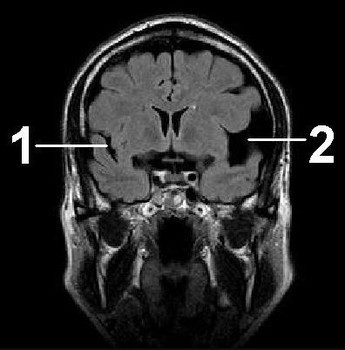

Давно известно, в каких местах головного мозга у новорожденного ребенка чаще всего обнаруживаются полости. Субэпендимальная псевдокиста образуется в боковых желудочках, а именно в их латеральных углах, а также в бороздке, разделяющей зрительный бугор (таламус) и хвостатые ядра (экстрапирамидные структуры). Именно эти образования и называют псевдокистами. Пузырьки, расположенные во всех других местах головного и спинного мозга, принято называть кистами.

Чтобы диагностировать наличие кист, поражающих область левого или правого бокового желудочка, проводится ряд инструментальных обследований.

Назначается, когда ребенку исполнится год. С помощью данной манипуляции можно установить двухстороннее поражение сосудистых сплетений. Но стоит отметить, что процедура проводится до того момента, пока не начнет закрываться передний родничок.